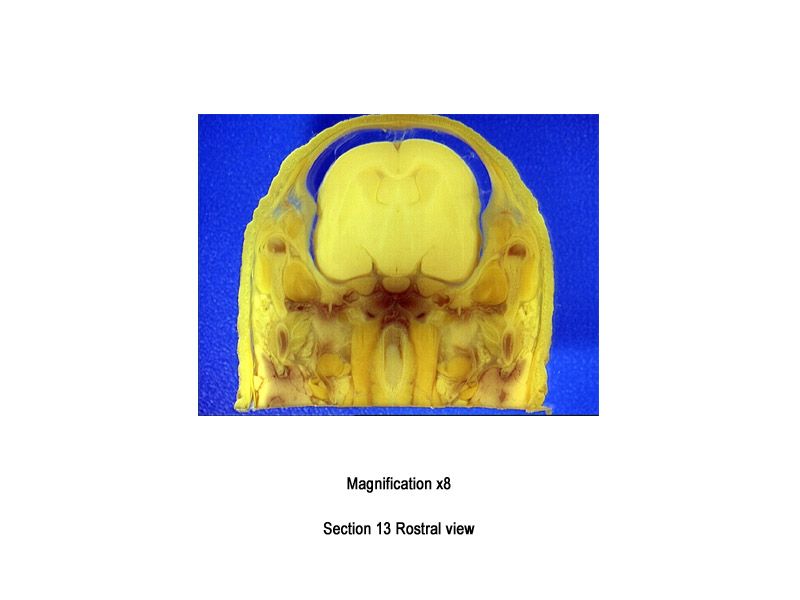

The images below show the normal appearance of Bouin's fluid fixed head sections in specimens at Day 29 of gestation (day mating observed = Day 0).

It is essential that both sides of each section is examined so that structures that exist is several sections can be visualised by the examiner in their mind as 3D.